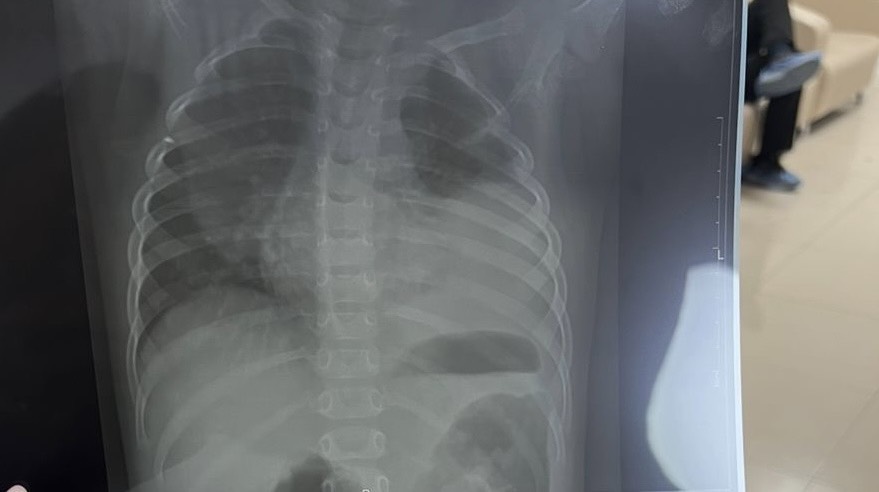

У старшей пневмония 😔 казалось бы температурила всего 4 дня и уже почти двусторонняя пневмония

Те дни когда сбивали температуру она бегала игралась. Сегодня вялая очень, тяжело дышит и плачет😭😭😭душа болит… сделали рентген и вот итог

У нас левосторонняя пневмония. Врач прописал декасан( ингаляция 7 дней). Теперь сижу и думаю, может к другому педиатру сходить, чтобы хорошее лечение назначили